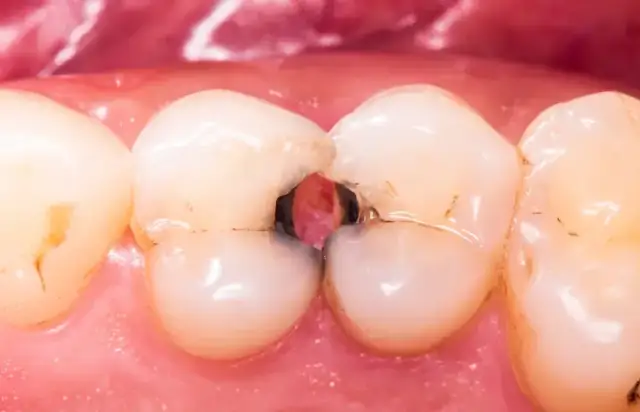

Warto pamiętać, że nie każda ekstrakcja jest taka sama. Proste usunięcie zęba, które można wykonać bez większej ingerencji w tkanki, zazwyczaj wiąże się z krótszym okresem bólu. Inaczej jest w przypadku ekstrakcji chirurgicznych, na przykład usuwania zatrzymanych ósemek, zębów zniszczonych próchnicą lub tych, które wymagają nacięcia dziąsła czy rozwiercenia kości. W takich sytuacjach gojenie trwa dłużej, a ból może być silniejszy i utrzymywać się nawet przez cały tydzień po zabiegu. To wynika z większego urazu tkanek i konieczności ich odbudowy.